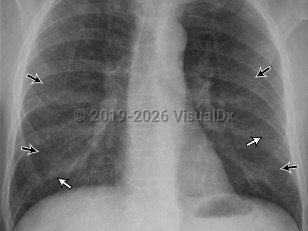

Acute respiratory distress syndromeAcute respiratory distress syndrome

Community-acquired pneumonia

Pulmonary edema

Pulmonary emphysemaPulmonary emphysema